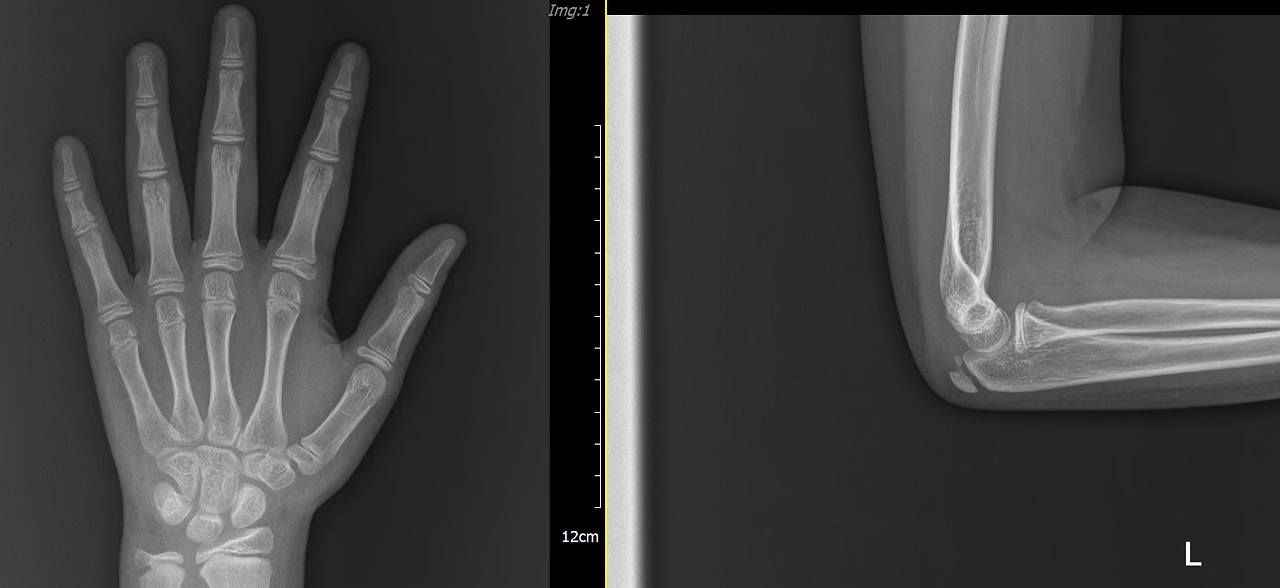

뼈나이 11세 3개월 (실제 나이보다 2년 이상 빠름)

현재 키 135.7cm (67 percentile - 100명 중 67번째로 현재는 키 큰 편)

뼈나이와 LH, E2 수치에 따른 예측 키 154~156cm

뼈나이와 LH, E2 수치에 따른 예측 초경 시기 : 1년 6개월 후에 초경 할 것으로 예상됩니다. (평균보다 1년 이상 빠름)